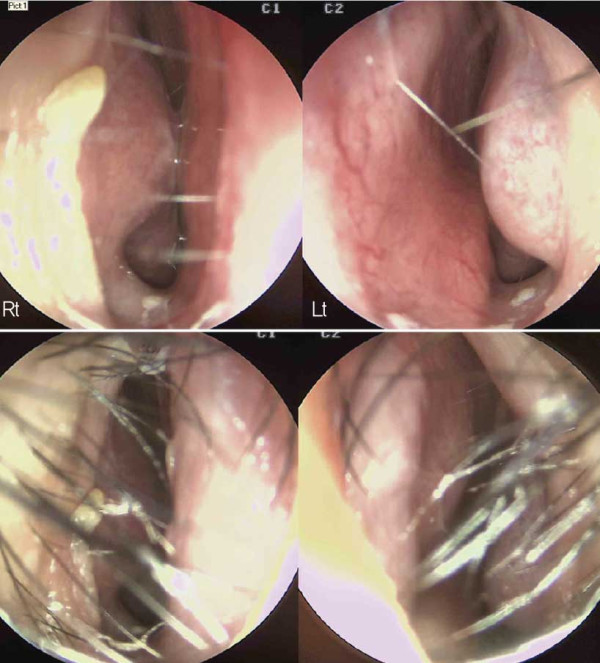

![]()

수술 전 내시경 사진. 비중격 상단부가 좌측으로 만곡되어 있으며, 미단부는

우측으로 전위된 모습이 관찰되었다. 비중격 미단부 변형 및 비익의 변형으로

인한 우측 비밸브 협착도 확인되었다

내시경 검사상 비중격 상단부가 좌측으로 만곡되고 미단 부가 우측으로 전위되어 있었다. 비중격 미단부와 비익의 선천적 변형으로 인한 우측 비밸브 협착도 관찰되어, 비중 격 및 비밸브 교정술과 하비갑개점막절제술을 계획하였다. 해당 환자는 외형적인 비대칭뿐만 아니라 기능적인 불 편함으로 인해 일상생활에서 어려움을 겪었다.

수술 중 채취한 재료. Bone-cartilage complex.

비중격 및 비밸브 교정 전. 비중격 상단부가 좌측으로 만곡되어 있으며,

미단부는 우측으로 전위되고, nasal spine은 우측으로 전위되어 있다.

수술장 소견상 cleft nose로 인해 nasal spine이 우측 으로 전위되어 있으며, 비중격 상단부는 좌측으로 만곡 되어 있고, 미단부는 우측으로 전위된 양상이었다. 또 한, 비익연골은 우측이 좁고 좌측은 낮고 퍼져 있었다. BC junction에서 nasal spine까지 비중격연골을 spreader graft를 시행하여 좌측 상단부의

만곡을 교정하였다.

비중격 및 비밸브 교정 후. 비중격을 nasal spine 좌측으로 이동시키고, bone을

이용해서 우측에 batten graft를 시행하여 미단부의 변형을 교정하였다. Costal

cartilage를 사용하여 batten-spreader graft를 시행하고 상단부의 만곡을

교정하였다.

늑연골의 일부를 박리한 후 nasal spine 좌측의 bone 결손 부위에 이식하여 코바닥의 높이를 조정하였다. 양측 비익연골은 연골 재배치를 통해 비대칭을 교정하 였으며, 고주파를 이용하여 양측 하비갑개 점막에 coblation을 시행하였다.